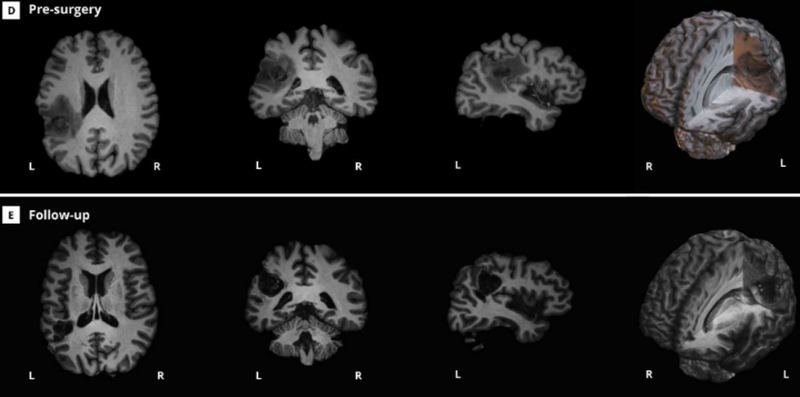

Allow me to introduce you to the subject of our case study, Patient AB. Part of the reason this study stood out to me was that I couldn't help but think AB sounded a lot like someone I could have met in college: 45 years old, a skilled programmer, multi-lingual, and a chess player with a pretty solid rating of 1950 ELO. Besides these traits and abilities, AB also had something else: A headache. Not just any headache, either, but a headache caused by a type of brain tumor called a Glioblastoma. You can see what his tumor looked like in the top row of the figure below - I'd say something to get you oriented towards what to look for, but I have a hunch you'll work it out on your own. While we're here, I'll also get straight to the point and refer you to the bottom row of the figure, too: The thing that AB's surgeons had to do was turn the brain that you see in the top row into the brain that you see in the bottom row. That is, the tumor would have to be resected.

Figure 3 (adapted from Cepero-Escribano et al., 2024) The top row depicts Patient AB's brain pre-operatively, with a large glioblastoma evident in the LH. The bottom row depicts the results of the surgery to remove this region. How do you make sure that the transition from the top row to the bottom row doesn't negatively impact AB's cognition?

This is no small thing to do, though. The obvious concern is that removing the tumor may also mean removing eloquent cortex, or portions of the brain that support specific functions like movement, sensation, or cognition. Remember all those things that I said AB was able to do? All of these were things that he also hoped to be able to do after the surgery - including playing chess at a fairly high level (much higher than your humble narrator at least). So what to do? I bring this kind of scenario up to my students a lot to remind them both that neuropsychology as a discipline is built on things we have learned from real people facing difficult circumstances imposed by injury or disease, and also that assessing cognitive abilities is difficult and important. How do you measure any complex ability like chess-playing or programming skill in a meaningful way? We have existing neuropsychological scales to assess cognition broadly in terms of memory, visual perception, and language, but what do you do to help a particular person preserve their specific skills when they have to undergo surgery on their brain? What the authors of this case study did for AB is quite cool, helping to ensure the preservation of his cognitive abilities while also offering some additional insights into what chess playing is in terms of a definition based on neural systems.